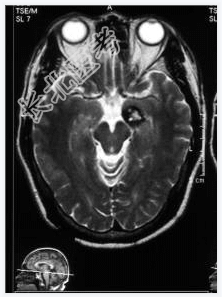

- [材料题] 患者,男性,52岁,间隙性发作情绪激动、乱语2年。一月前外院CT提示左海马高密度影,性质待定。做头颅MRI检查。